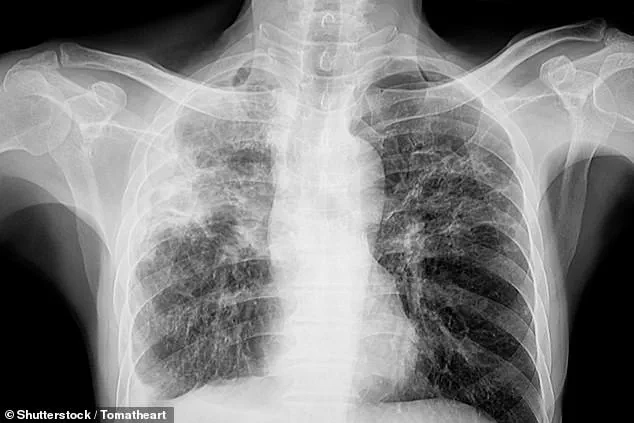

The symptoms of TB can vary depending on the stage of the disease.

In its early phases, individuals may experience a persistent cough that lasts for weeks, often accompanied by the coughing up of blood or chest pain.

Other common symptoms include unexplained weight loss, loss of appetite, fever, and night sweats.

As the disease progresses, patients may develop severe breathing difficulties, extensive lung damage, and the infection may spread to other organs such as the liver or spine, leading to localized pain.

In the most advanced stages, TB can be fatal due to respiratory failure or the inability of the lungs to provide sufficient oxygen to the body.